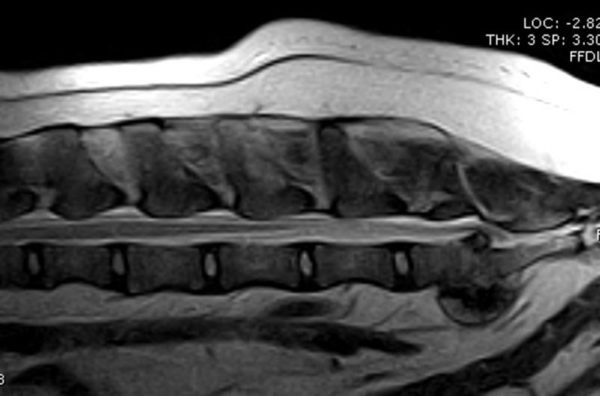

MRI image of a dog's lumbosacral spine.

Dog lumbosacral spine